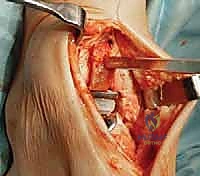

4. تركيب المفصل الصناعي (Implantation)

يتكون مفصل الكاحل الصناعي الحديث عادة من ثلاثة أجزاء:

* قطعة معدنية علوية: تُثبت في عظمة الظنبوب (الساق).

* قطعة معدنية سفلية: تُثبت في عظمة الكاحل.

* قطعة بلاستيكية (بولي إيثيلين عالي الكثافة): توضع بين القطعتين المعدنيتين لتنزلق بسلاسة وتمتص الصدمات، محاكيةً وظيفة الغضروف الطبيعي.

يتم تثبيت هذه الأجزاء بإحكام (إما عن طريق الضغط المباشر لتشجيع نمو العظم حولها، أو باستخدام أسمنت طبي خاص).

5. إغلاق الجرح والجبيرة

بعد التأكد من استقرار المفصل الجديد ومدى حركته الممتاز، يقوم د. هطيف بإغلاق الشق الجراحي باستخدام خيوط تجميلية دقيقة لتقليل الندبات. يتم وضع الكاحل في جبيرة أو حذاء طبي خاص لحمايته خلال الأسابيع الأولى من التعافي.